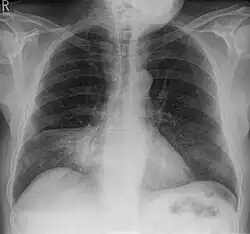

- (Aero)Bronchopneumogramm, positives: In einer infiltrierten Lunge (in der Regel bei einer Lungenentzündung) zeichnen sich die luftgefüllten Bronchien auf der Röntgenaufnahme des Brustkorbes dunkel auf der infiltrierten, hellen Lunge ab.

- Silhouettenphänomen: Lungenverdichtungen, die vorne liegen, lösen visuell die Herzkontur auf, während hinten liegende Infiltrate die Herzkontur scharf erkennbar lassen. So kann auch ohne seitliche Aufnahme zwischen einer Mittellappenpneumonie (vorne) und einer Unterlappenpneumonie (hinten) unterschieden werden.